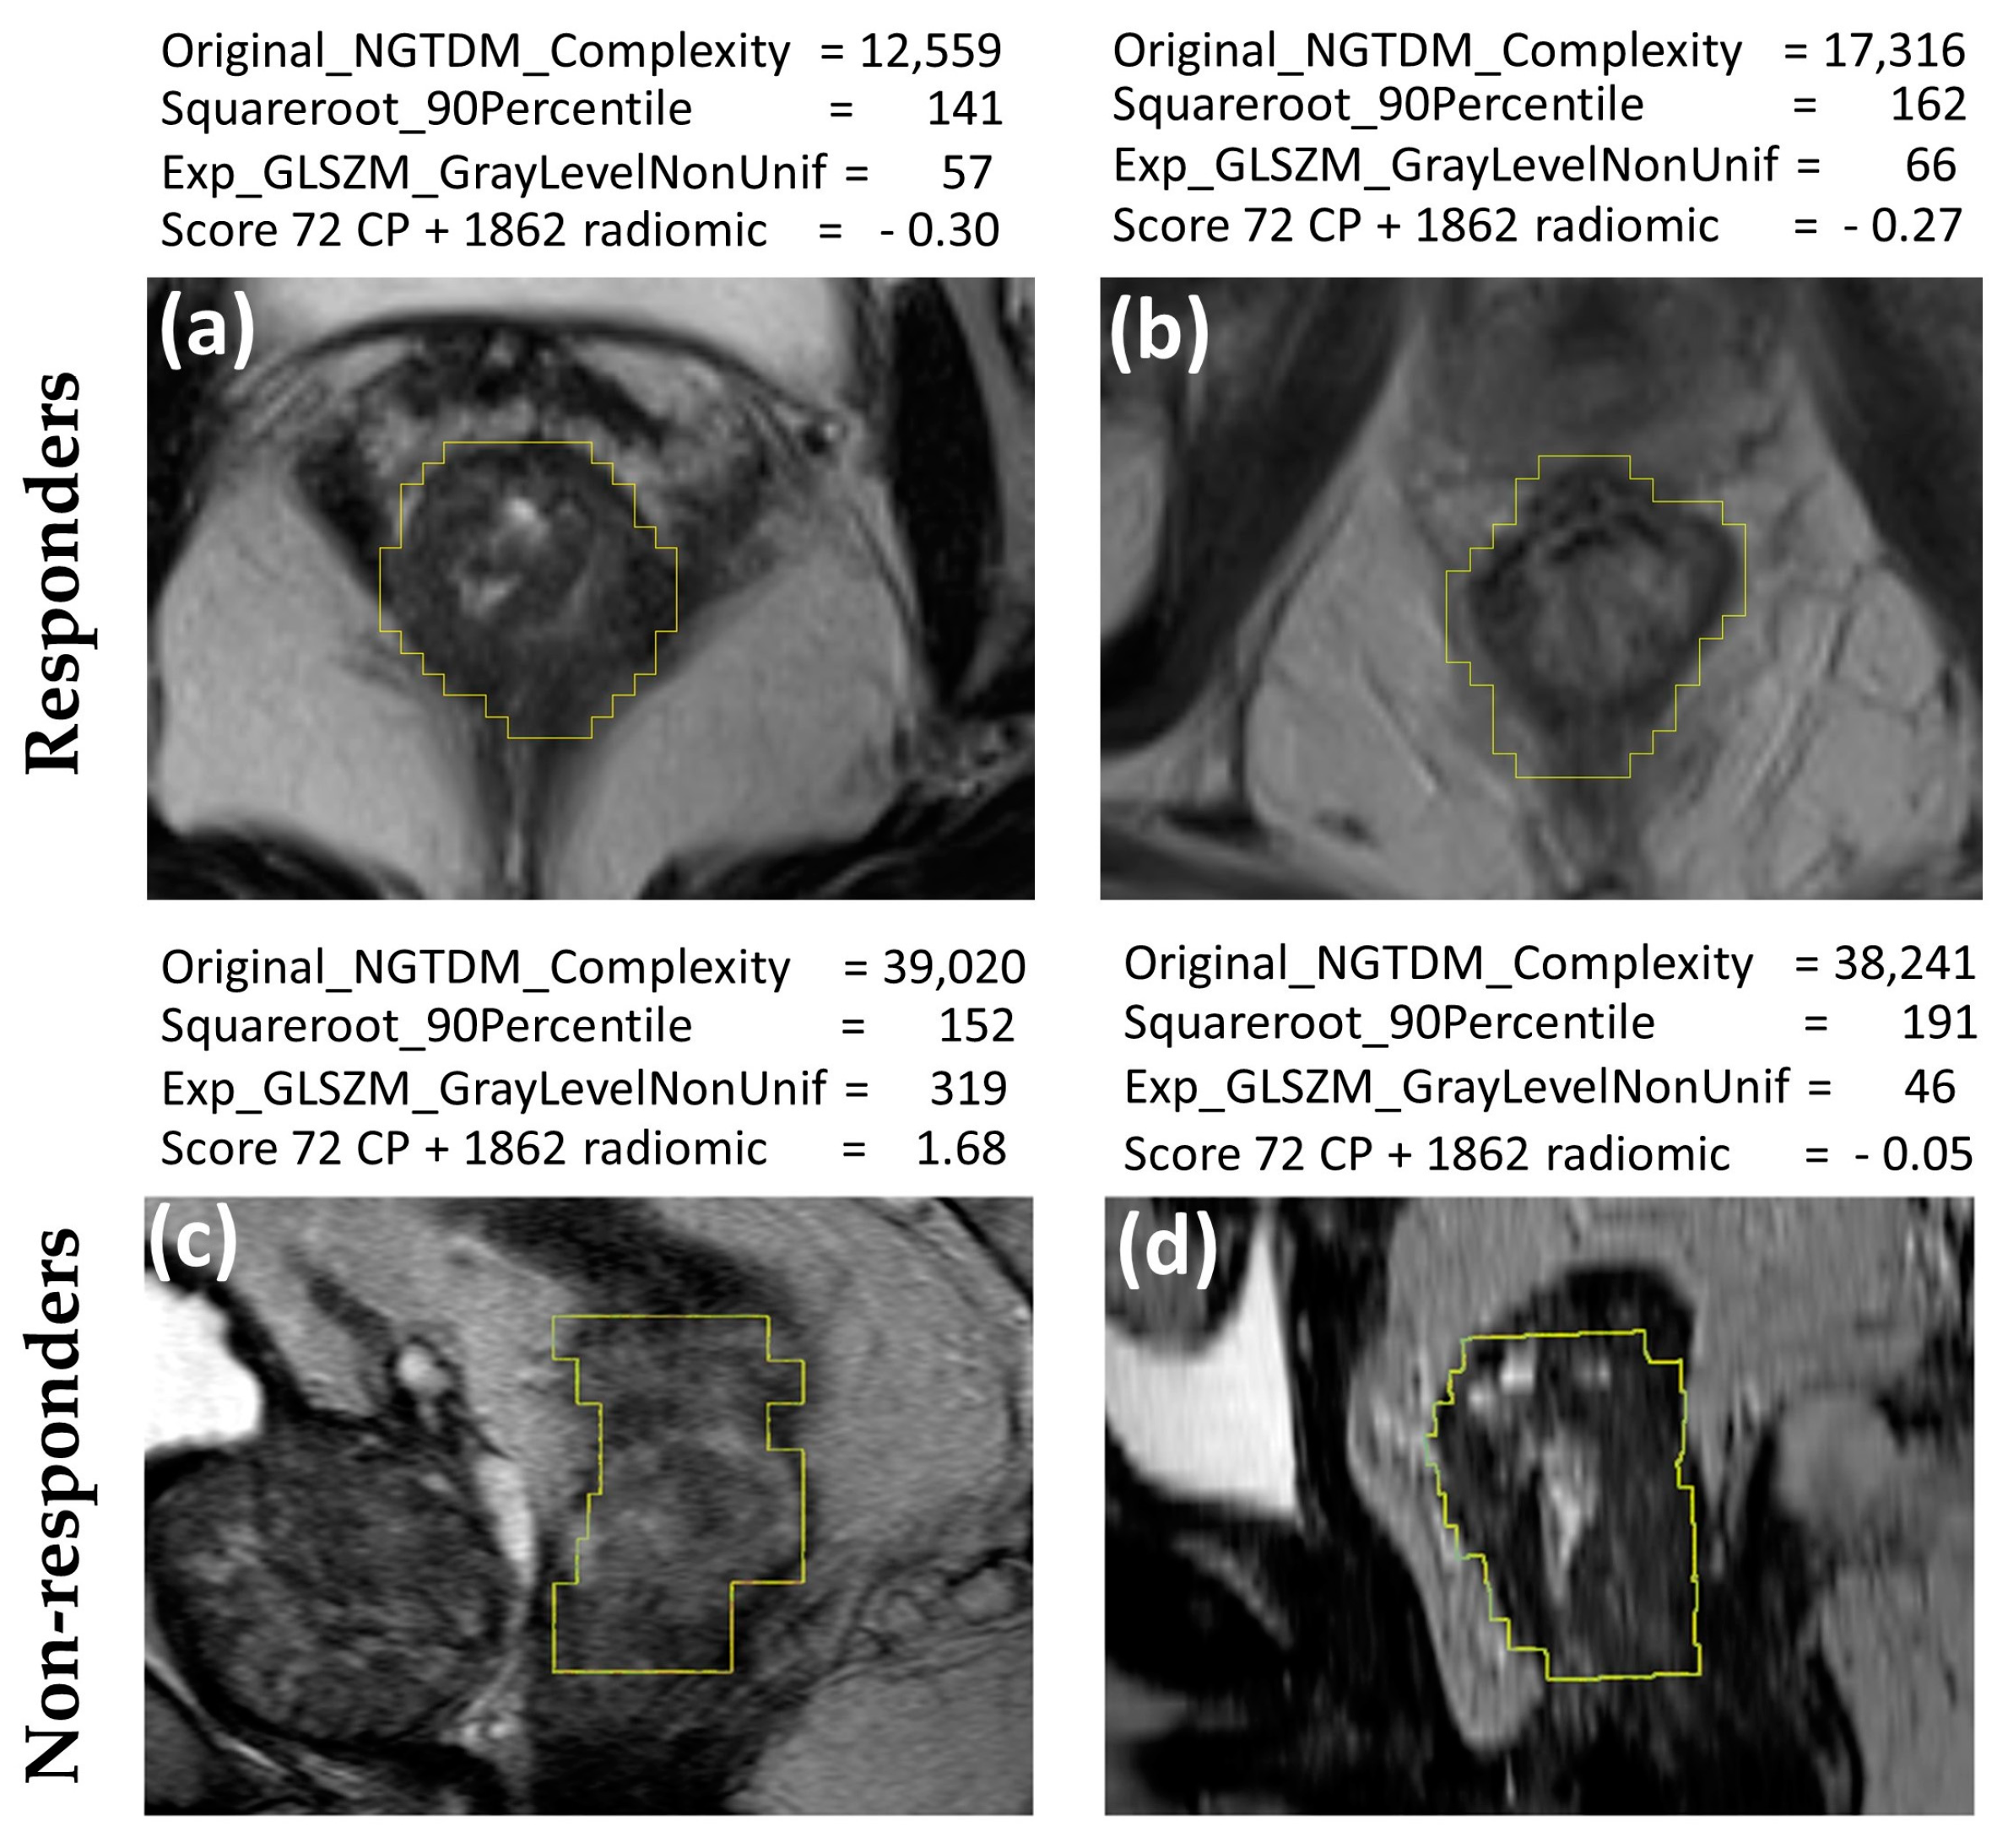

| Original_NGTDM_Complexity | Coefficient = 0.385 0.111–0.581 | p = 0.002 |

| Model: from 72 CP + 1862 radiomics features R2 = 0.47 | ||

| Mucinous histological type | Coefficient = 0.258 0.068–0.431 | p = 0.009 |

| Initial basophil count | Coefficient = 0.384 0.270–1.207 | p = 0.0014 |

| Type of CRM involvement | Coefficient = 0.319 0.071–0.542 | p = 0.008 |

| Squareroot_firstorder_90Percentile | Coefficient = 0.483 0.262–0.659 | p = 0.001 |

| Exponential_GLSZM_GrayLevelNonUniformity | Coefficient = 0.377 0.178–0.528 | p = 0.001 |